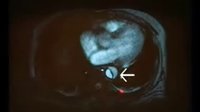

急性ST段抬高心肌梗死

04损伤型心肌梗死心电图改变